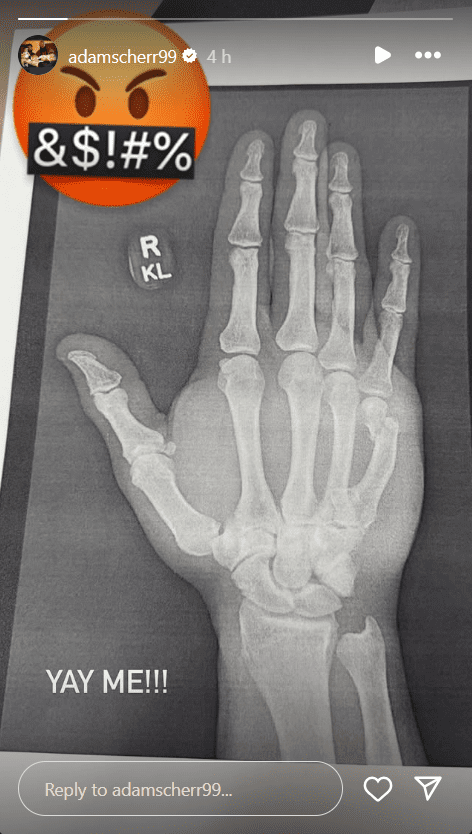

The Monster Among Monsters took to his Instagram story and uploaded a photo of an X-ray, revealing that he suffered a broken wrist injury. He included an angry emoji.

You can view an image of the x-ray he shared of the injury below: